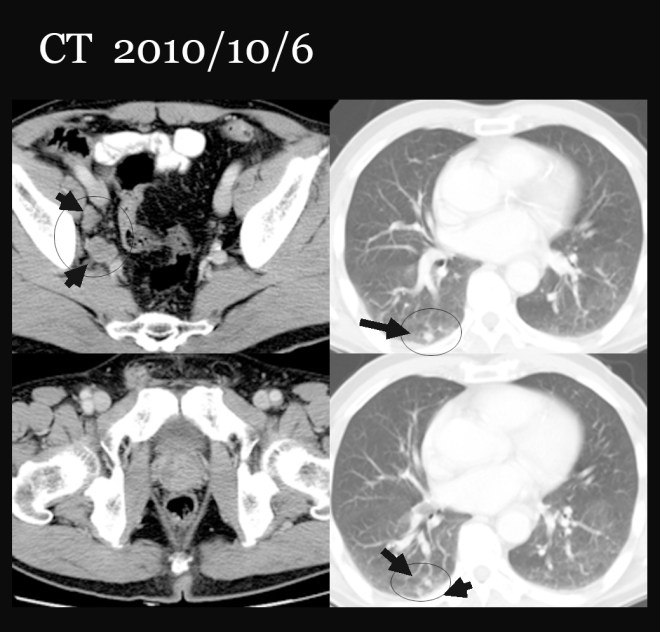

이번 원고에서 소개하려는 환자는 74세의 남성으로, 2010년 10월 전립선암 4기 골반벽전이 폐전이(prostatic cancer IV stage  with lung metastasis)로 아산병원에서 진단을 받았다. 초기에   bicalutamide(상품명 casodex)를 복용하면서 초기에 GnRH agonist인 zoladex 주사를 한차례 시행하였다. 그리고  2010년 11월 초에 반룡인수 clinic으로 방문하였다.

• 2010/10 : 건강검진 전립선암 발견 (biopsy proven prostatic cancer stage IV multiple lung and pelvic lymph nodes metastasis)

2010/10/6  CT 복부와 골반부

• 조직검사로 입증된 전립선암

• 우측obturator muscle, 우측 external, common iliac, paraaortic, retrocavla and retrocrural 부위의 림프절 전이

• 우측 폐의 하엽의 뒷벽에 전이로 보이는 폐의 덩어리들

• 신장에 4cm에 이르는 단순 양성 물혹

• 골반에 양성으로 보이는 뼈의 이상 부위

2010/10/14  CT 가슴사진

• 여러 개의 작은 RML(우측중엽)과 RLL(우측 하엽)의 덩어리들로 전이로 보인다.

• 우측 빗장뼈 위로 1.6cm 가량의 커져 있는 림프절이 보인다. 아마도 전이로 보인다.

• 왼쪽의 신장에 물혹

• 특별한 흉추의 뼈의 이상은 보이지 않음

당시 환자의 CT를 간략하게 소개해 본다.

정영기1-2.jpg

• 우측 폐의 우측 하엽에 보이는 하얀 점들(검은 화살표)이 폐전이 된 암임

• 전립선은 비대되어 있다.

• 좌측 골반뼈 주위에 림프절 전이(검은 화살표)가 보인다.